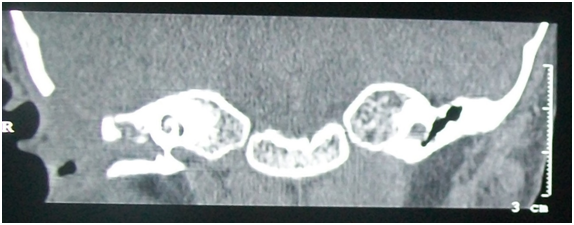

High resolution CT of the temporal bone showed a soft tissue density in attic, aditus and antrum. The dural plate and sinus plate were found to be eroded (Figures 4&5).

Figure 5 HRCT Temporal bone (coronal view) shows soft tissue density in right middle ear, attic and external auditory canal.